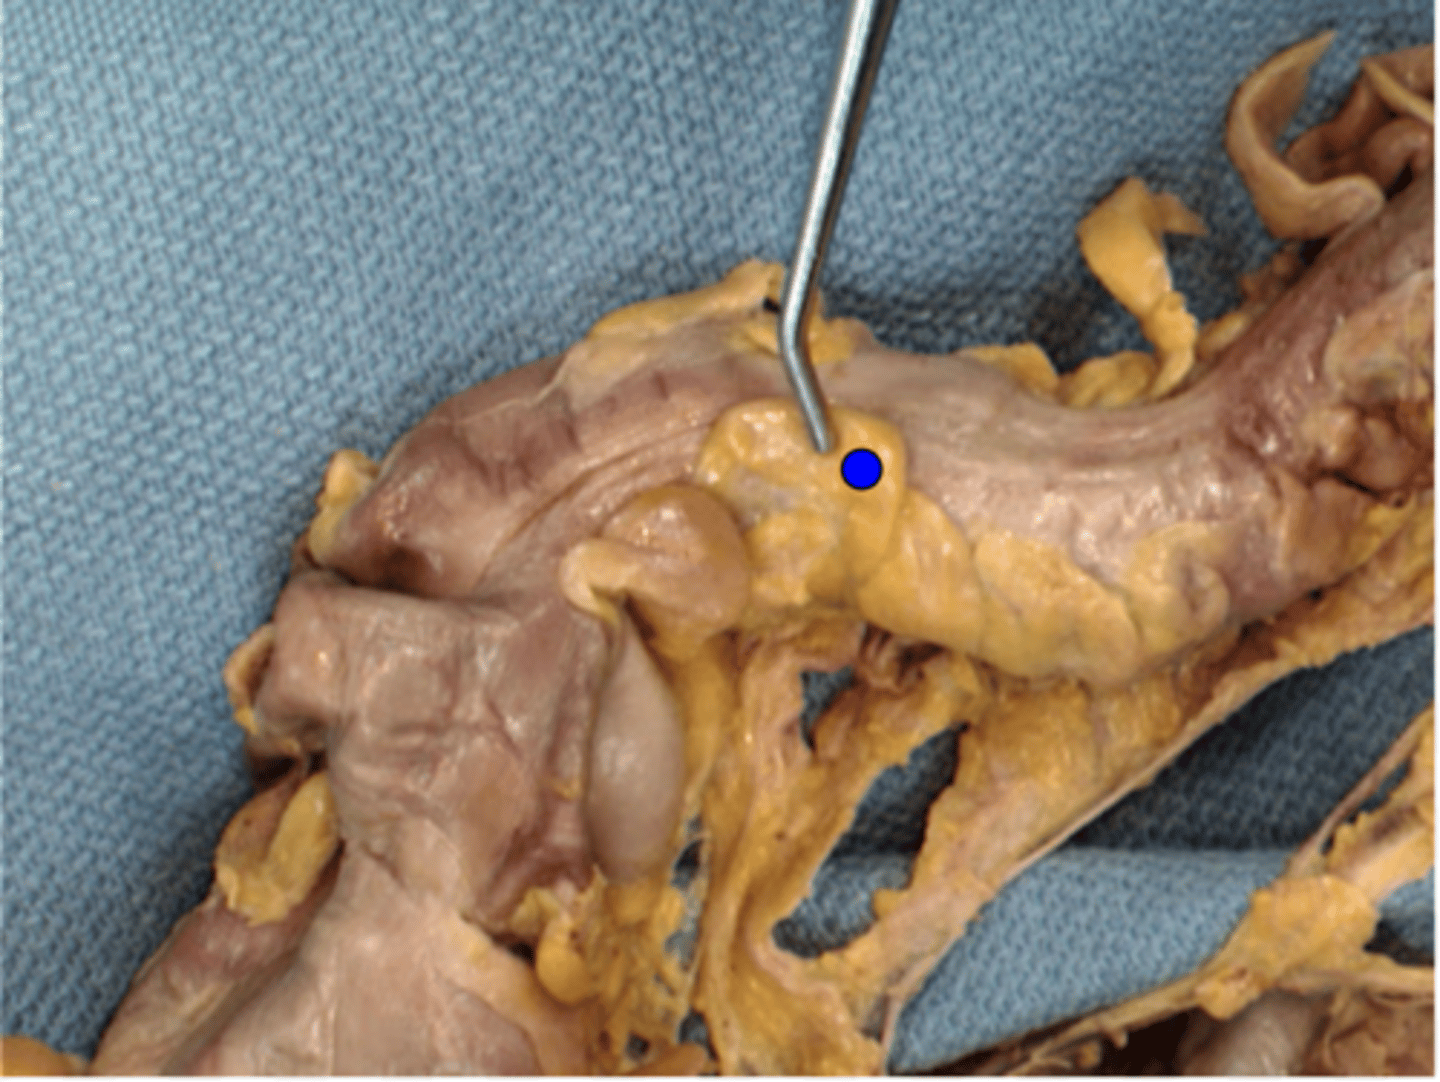

Ileocecal Valve